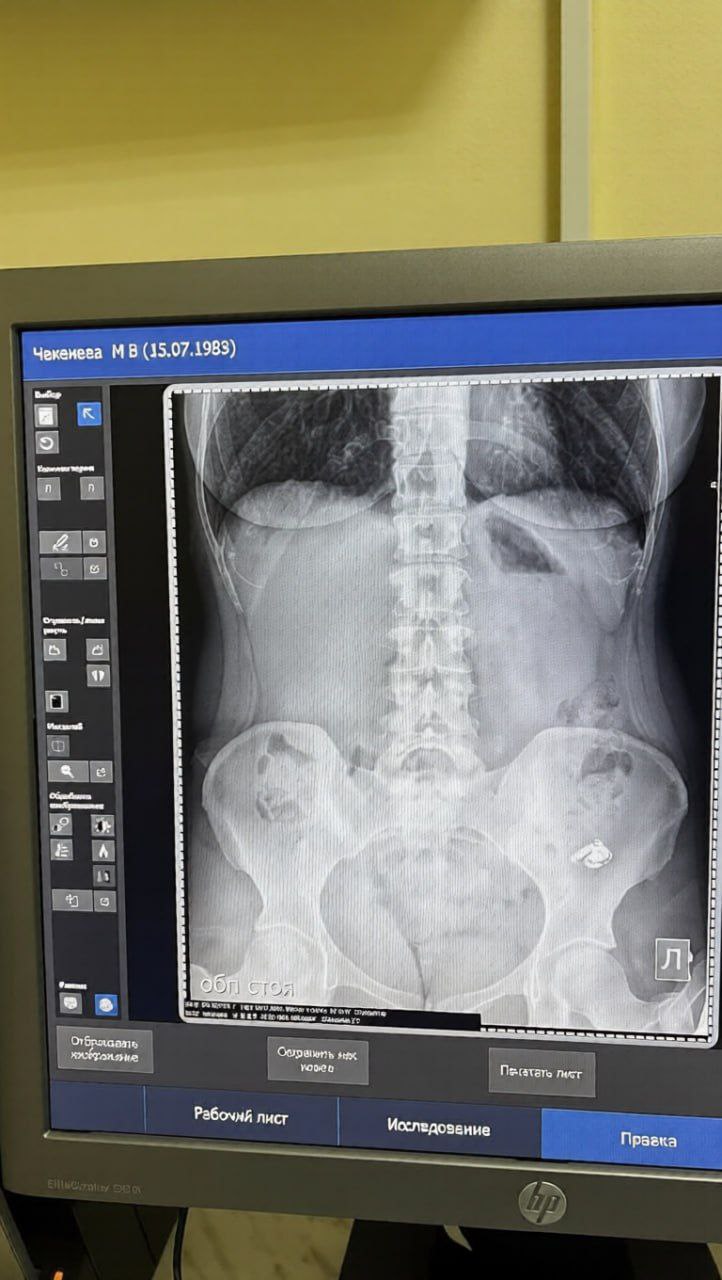

Девушка заранее закинула в карман таблетки, чтобы выпить их за обедом. В нужный момент, не глядя, закинула всё в рот и запила водой.

Уже позже девушка полезла за наушником в карман и поняла, что он ушёл внутрь вместе с лекарствами.

В больнице сделали рентген и посоветовали ждать «естественного исхода». На следующий день наушник вышел сам и, что самое смешное, остался рабочим.